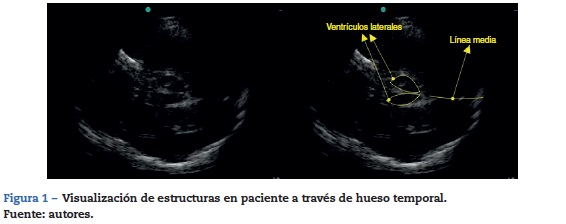

El desplazamiento de la línea media cerebral es uno de los parámetros que denota severidad en patologías neurológicas y en ocasiones define el manejo quirúrgico. Reportes de casos han mostrado que es posible visualizar la línea media en la ventana ósea a través de la escama del hueso temporal13. Se requiere un transductor de baja frecuencia (1 a 5 mhz) y software para doppler trascraneano que optimiza las imágenes cuando se realiza ultrasonografía de cerebro.

En esencia, es la misma técnica para realizar un doppler trascraneano color, solo que las estructuras serán visualizadas en modoB (fig. 1). Se pueden visualizar los ventrículos laterales y la línea media; esta última se ha reportado desviada en pacientes con ataque cerebrovascular, hematomas dura-les y ocasionalmente hemorragias gangliobasales. Se pueden localizar catéteres de derivación con esta técnica14,15. Es importante recordar que hasta un 15% de los pacientes no tienen una buena ventana ultrasonográfica, por lo que no serán visibles estas estructuras16.